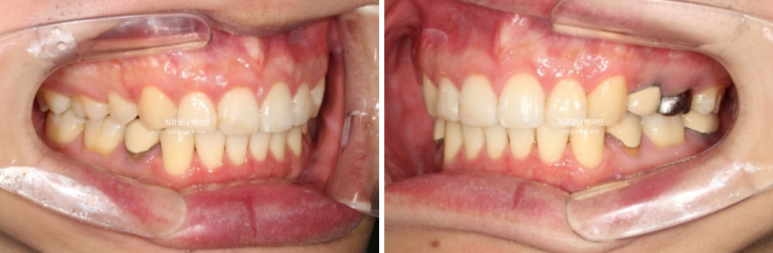

2022.12월 돌출입을 주소로 내원한 환자분 입니다.

앞니 중심선이 어긋나있고 앞니 기울어짐이 보입니다.

2022.12

앞니가 상당히 뻗쳐있는 상태 뻗침과 돌출이 심해서 입이 잘 안다물어지는 상태였고 골격분선상 골격성 2급 부정교합 (무턱)도 있습니다.

앞니가 뻗쳐있는 심한 돌출입은 당연히 발치교정을 해야합니다.

인비절라인 치료 선택하셨고 치료에 들어갔습니다.